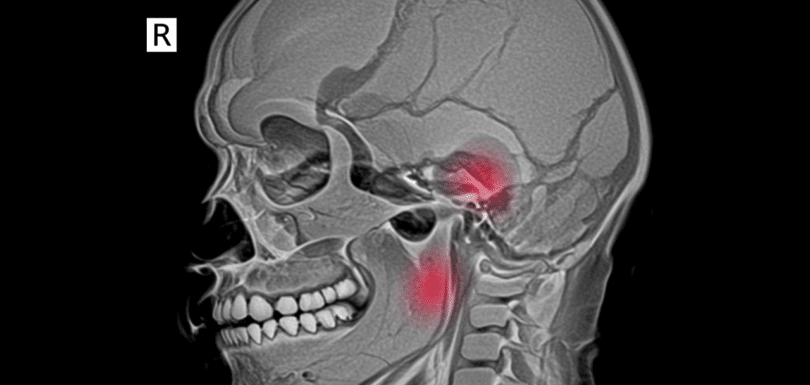

Head CT Stroke Hemorrhage Trauma Odessa TX

Head CT for Stroke, Hemorrhage, or Trauma Emergency Treatment in Odessa TX | Priority ER – 24/7 Head CT for stroke, hemorrhage, or trauma is a critical diagnostic test required immediately when experiencing sudden weakness, severe headache, altered consciousness, head injury, or neurological symptoms. Priority ER provides 24/7 emergency head CT imaging with zero wait […]